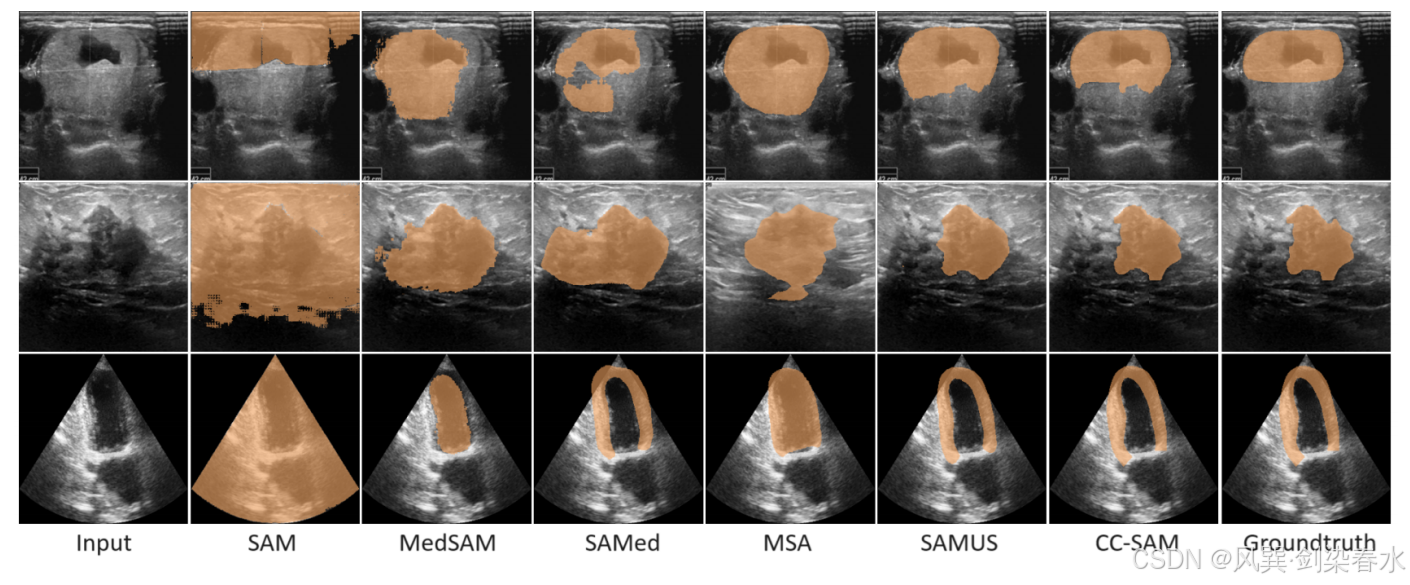

Figure 6 | CC-SAM 与 SOTA 基础医学分割模型之间的定性比较: